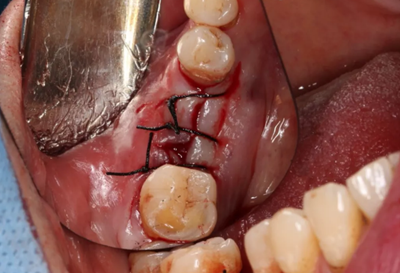

14、植骨手術(shù)過程

刮除肉芽組織及種植體表面清潔后,種植體唇側(cè)骨缺損區(qū)植入人工骨粉。

(攝于2017年8月10日)

引導(dǎo)骨再生

無張力間斷縫合切口。